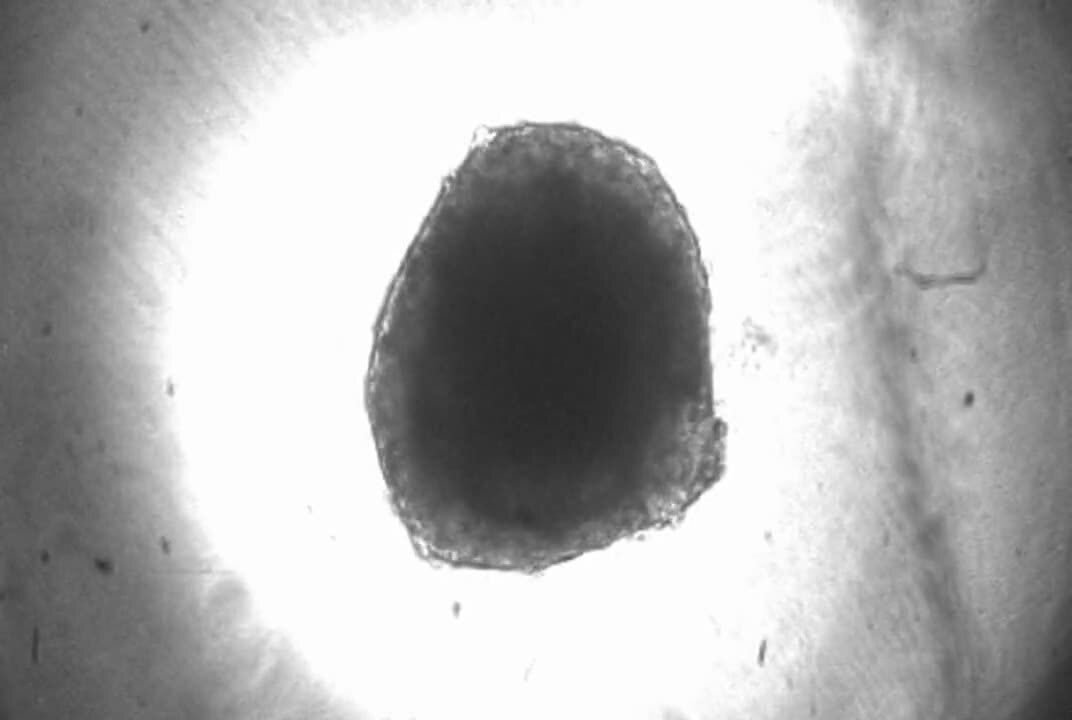

Den nya modellen består av mänskliga celler och innehåller tre olika typer av hjärtceller: kardiomyocyter, hjärtats muskelceller, fibroblaster som fungerar som stödjeceller och endotelceller som finns på blodkärlens insida.

– Tillsammans fungerar cellerna nästan som ett hjärta i miniatyr och vävnaden drar ihop sig regelbundet, precis som ett hjärta som slår, säger Geena Paramel.

I studien undersökte forskarna hur hjärtvävnaden reagerar på inflammation. De framkallade en inflammatorisk reaktion i den tredimensionella hjärtvävnaden med hjälp av lipopolysackarider, molekyler från bakterier som aktiverar vårt immunförsvar.

I studien har forskarna utvecklat en konstgjord tredimensionell hjärtvävnad som består av kardiomyocyter, fibroblaster och endotelceller, för att studera inflammation.

Kardiomyocyter är hjärtats muskelceller, fibroblaster är stödjeceller och endotelceller finns på blodkärlens insida.